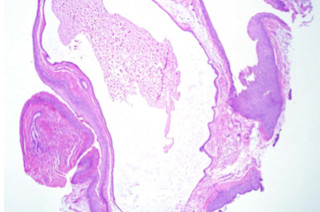

"A cyst is present in Reinke's space in a true vocal cord biopsy.It contains mucus inspisated in a shape resembling a puppy (Figure 1). The cyst is lined by columnar epithelium (Figure 2). We diagnosed it as a Mucus Retention Cyst of the Vocal Cord. Mucus retention cyst of the true vocal cord arises from a blocked mucus-producing gland in this area."

A Well-Differentiated Squamous Cell Basset Hound

"A sad-looking basset hound invading the dermis."

Figure 1. A well-differentiated, but sad-looking squamous cell Basset hound invading the dermis